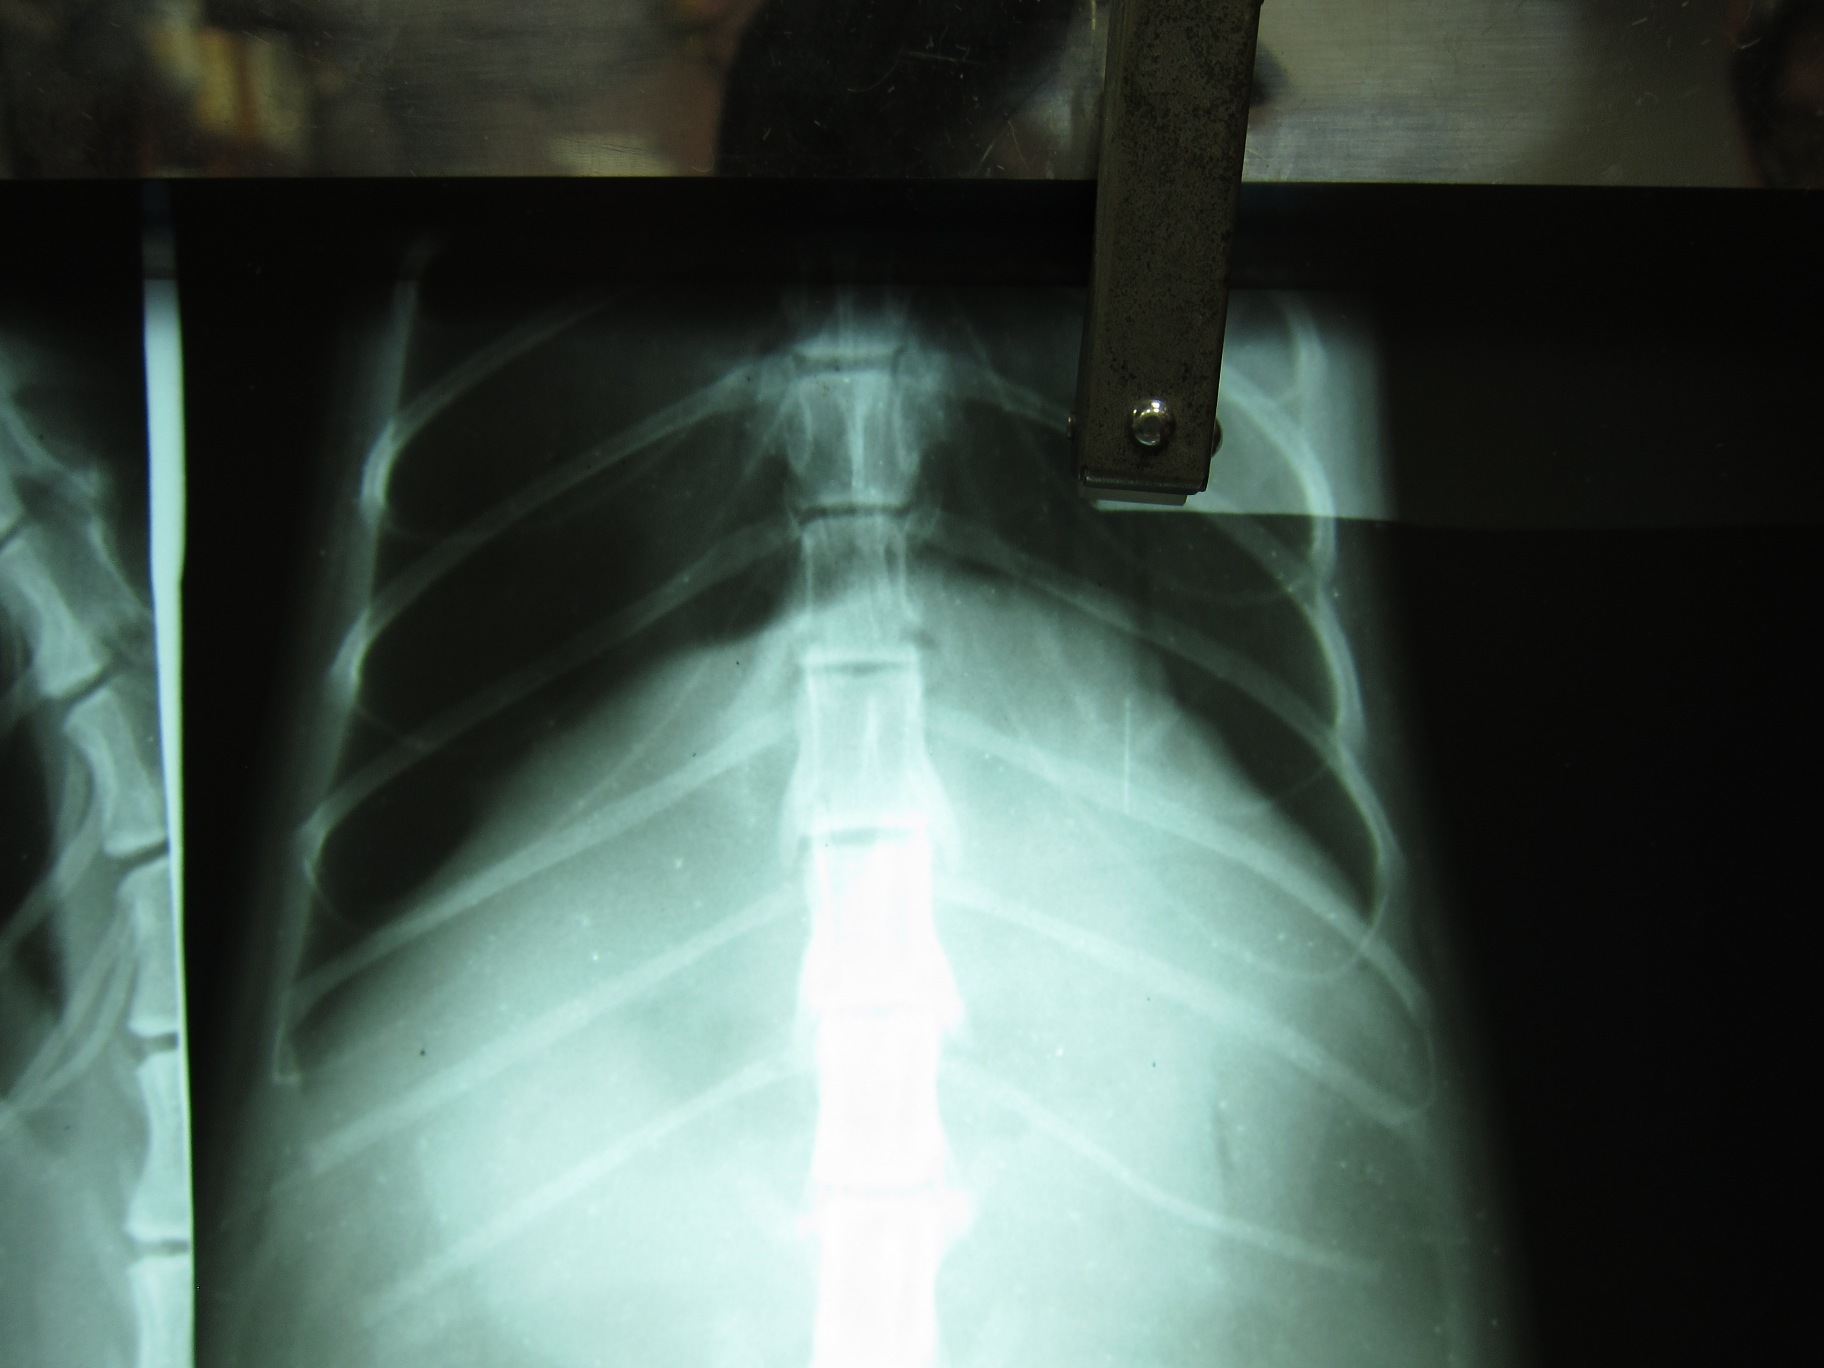

照完X光後,醫師發現有內出血,胰臟破裂,氣胸,有一部分的肝也破了,腎臟也受傷等等狀況。因為實在傷得很重,心跳跟呼吸也都漸漸微弱,只能靠吸氧氣支撐。不過最後還是撐不住就走了。動物近況說明: 他本來是社區貓,一直都跟不太友善的人類相安無事。